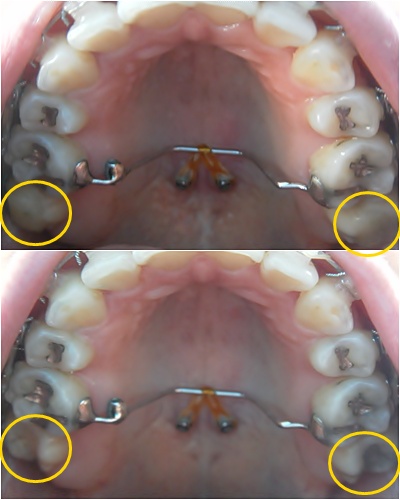

상악 제일 안쪽 어금니 바이트 블럭 제거했어요~ 이번 월치료는 바이트 블럭 제거하는 걸로 진료 끝~ + _+

바이트 블럭 제거하기 전과 후 비교사진입니당 :D

헐... 바이트 블럭 제거하고 나니 며칠동안은 어금니로 씹는 게 좀 어색했어요~ ㅎㅎ